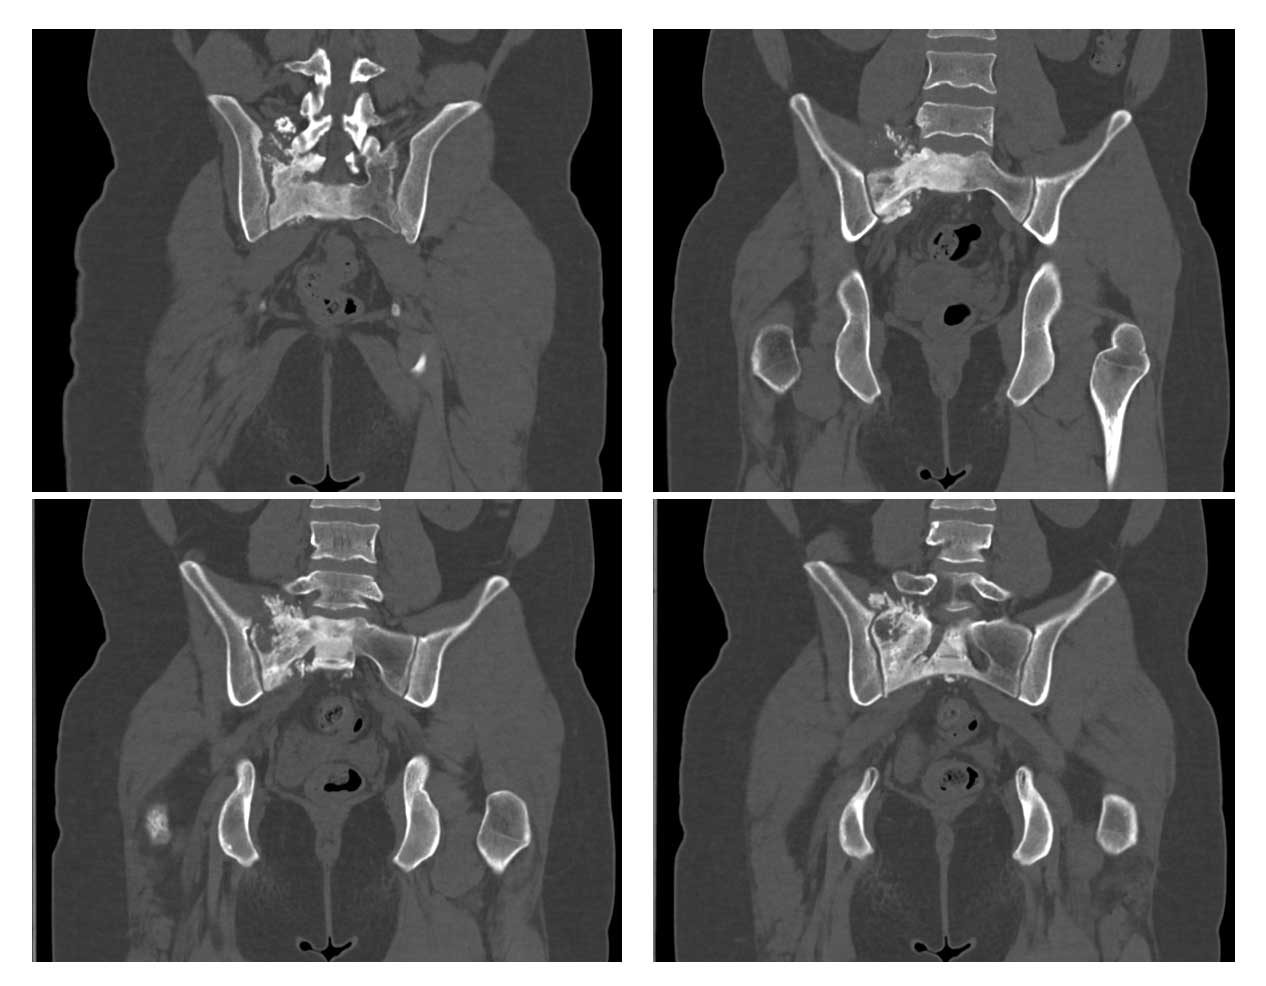

Ameliyat Öncesi: Tomografide sağ sakroiliak bölgede düzensizlik ve sklerozun eşlik ettiği tümör dokusu görülmekte.